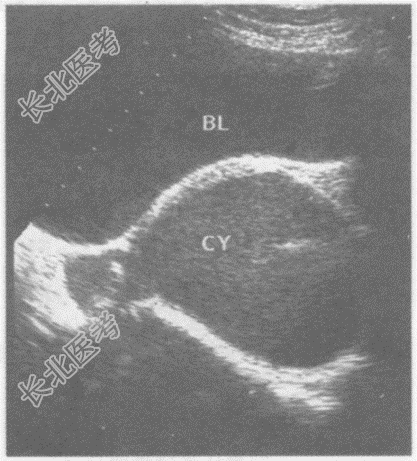

- 单项选择题临床资料:女性, 28岁,常规体检。

超声综合描述: 子宫形态、大小正常,肌层回声均匀。子宫右后方可见不规则无回声区, 边界清晰,囊壁厚, 内透声不清亮,可见点状中强回声。

其超声提示: A、右卵巢囊肿蒂扭转

B、盆腔脓肿

C、右卵巢巧克力囊肿

D、右输卵管积液

E、卵巢癌